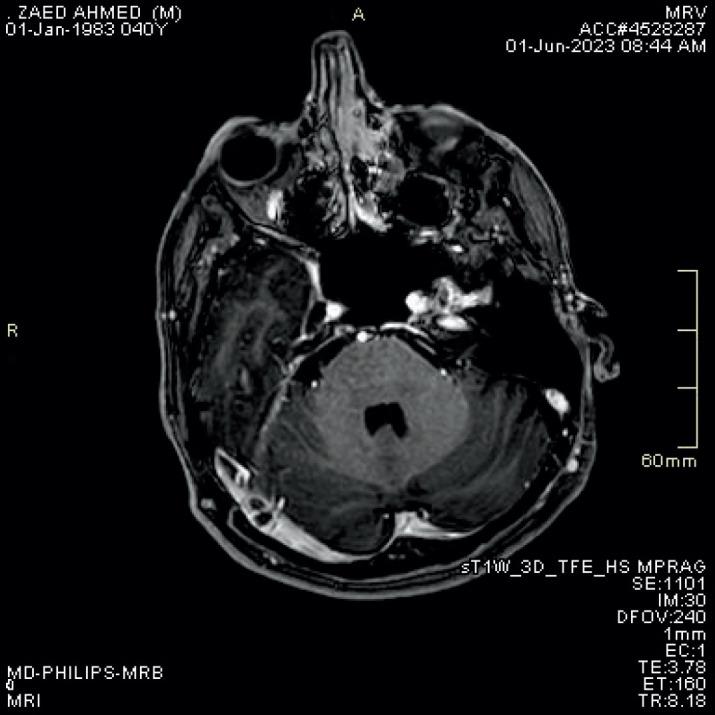

Post -contrast Three -dimensional MP RAGE T1WI Sequence Compared to Brain MRV Sequence for Diagnosing Brain Sinus Venous Thrombosis.

The aim of this article was to compare the accuracy of MRV TOF and post contrast MP-RAGE sequences in diagnosis of cerebral sinus venous thrombosis.

The guidelines and regulations of studies conducted in Royal medical services were followed. 68 females and 32 males with age range between 19 and 52 years. All patients underwent brain MRI for evaluation of cerebral sinus thrombosis, all studies were done on seimens skyra 3 Tesla machine with standardized protocol including 2 D TOF MRV, axial T2WI, axial FLAIR, Axial T1, SWI and diffusion weighted images along with 3D MP-RAGE post contrast. Images were reviewed by two well experienced neuroradiologists (Maysoon and Qamar) in separate sessions, each MRI sequence was reported separately without knowing patients name or clinical history. The results for T2 WI, SWI, MRV TOF and MP-RAGE post contrast were reported. We used a confidence level score to standardize the results. Then the results were analyzed using simple statistical methods.